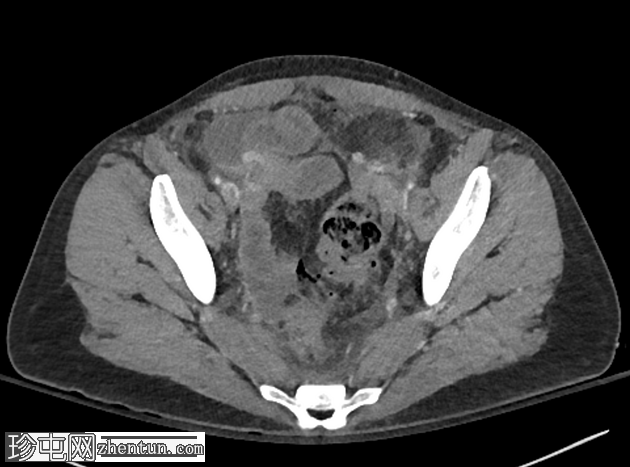

轴向 C+ 门静脉期

乙状结肠壁增厚且衰减降低,存在多个憩室

乙状结肠附近有气腹气泡,以及腔外粪便

弥漫性气腹

腹腔内游离液体,腹膜层增厚,提示有腹膜炎

发现符合穿孔性憩室炎(IV 期改良 Hinchey 分类)。

肠管扩张,口径无变化,可能是反应性无动力性肠梗阻

结肠壁弥漫性增厚,造影增强,可能是反应性结肠炎

本例患者为一名年轻女性,出现弥漫性腹痛。虽然这种疼痛可能有多种原因,但 CT 成像显示有复杂的穿孔性憩室炎(粪便性腹膜炎 - IV 期,改良 Hinchey 分类),手术证实了这一点。